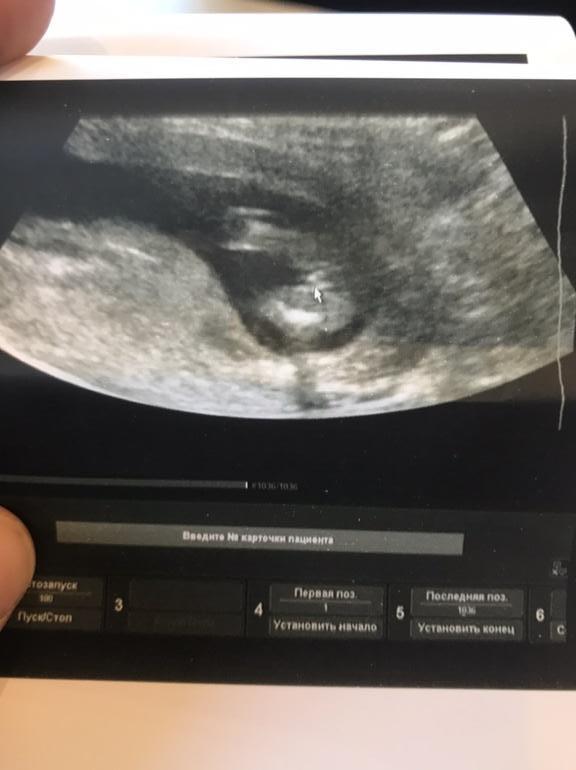

Пол в 14-15 недель.

С малышом все впорядке)Размеры на 14-15 недель,как и по сроку)

Врач предположила пол)Но мне что-то не верится🙈как-то не очень уверенно она это сказала,да и я наверное поверю, когда родится только)

Сказала:Скорее всего девочка)

Вот фото)Что правда?По-моему вообще ничего непонятно🙈🙈🙈старшим на таком сроке делала узи и не знаю,что должно быть видно)